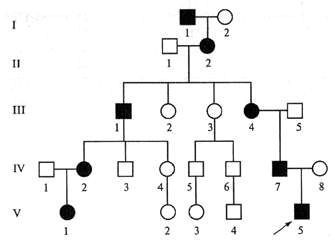

Neonatalnaya forma sindroma marfana klinicheskoe opisanie i kompleksnyj podhod k diagnostike i lecheniyu tema nauchnoj stati po klinicheskoj medicine chitajte besplatno tekst nauchno issledovatelskoj raboty v elektronnoj biblioteke kiberleninka (Тип файлу jpg)

Neonatalnaya Forma Sindroma Marfana Klinicheskoe Opisanie I Kompleksnyj Podhod K Diagnostike I Lecheniyu Tema Nauchnoj Stati Po Klinicheskoj Medicine Chitajte Besplatno Tekst Nauchno Issledovatelskoj Raboty V Elektronnoj Biblioteke Kiberleninka

Neonatalnaya forma sindroma marfana klinicheskoe opisanie i kompleksnyj podhod k diagnostike i lecheniyu tema nauchnoj stati po klinicheskoj medicine chitajte besplatno tekst nauchno issledovatelskoj raboty v elektronnoj biblioteke kiberleninka (Тип файлу jpg)

Neonatalnaya Forma Sindroma Marfana Klinicheskoe Opisanie I Kompleksnyj Podhod K Diagnostike I Lecheniyu Tema Nauchnoj Stati Po Klinicheskoj Medicine Chitajte Besplatno Tekst Nauchno Issledovatelskoj Raboty V Elektronnoj Biblioteke Kiberleninka